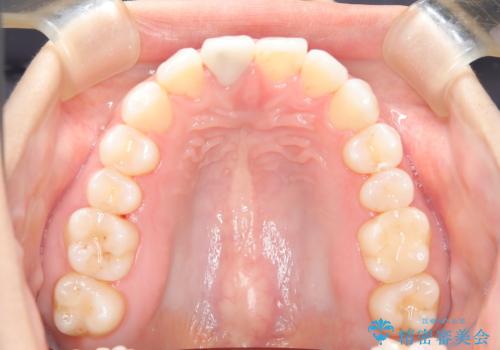

根管治療と並行して矯正を マウスピース治療

- 前歯のガタつき、変色を主訴に来院された患者様です。術前診査のCT撮影にて、変色した前歯の根の先に病巣があることが判明しました。そこで、マウスピースによる矯正治療と、前歯の根管治療、かぶせ物のやり直し治療を並行して行いました。